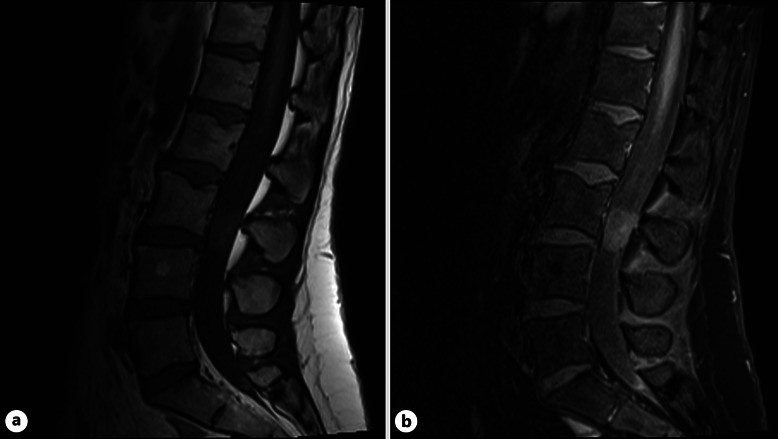

Case summary: A 46-year-old female presented with a 3-month history of worsening back pain. Reduced sensation on the right side in L1, L2, and per rectum was found on examination. MRI displayed a L3 IDEM mass. Background was significant for childhood PA, debulked at age 8 and 13. Right L3 hemilaminectomy and subtotal resection was performed. The mass was found to be composed of pleomorphic astroglial cells and was glial fibrillary acidic protein-positive with a fusion between exon 16 of KIAA1549 and exon 9 of BRAF. A recurrence of pilocytic astrocytoma in the lumbar spine was diagnosed, over 38 years after previous treatment.

Abstract Image